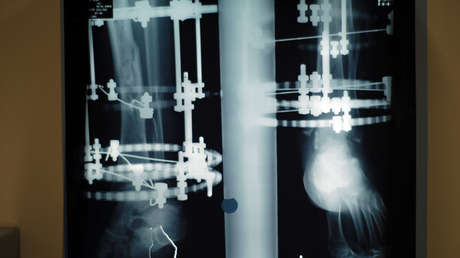

La técnica, conocida como alargamiento óseo por distracción, consiste en cortar el hueso y fijarlo a un dispositivo externo o interno que se va ajustando milimétricamente cada día. Fue ideada por el cirujano ortopédico soviético Gavriil Ilizárov en los años 50.

El proceso estimula la formación de nuevo tejido óseo en la separación, pero se extende por meses, requiriendo una fisioterapia intensiva. Los pacientes deben estar preparados para un período de incapacidad significativa y un dolor persistente, con riesgos inherentes como infecciones, daños nerviosos o artritis, entre otros.